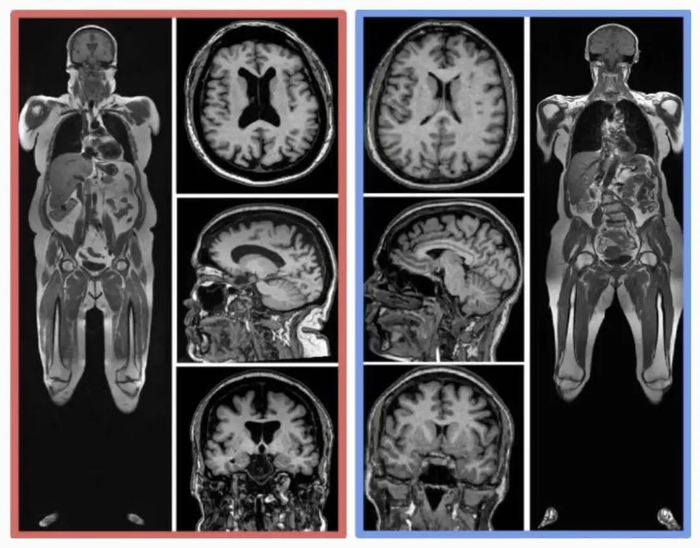

同样年龄的人,腹部脂肪(皮下和内脏)更多,脑部图像显示出更小的脑容量。

左侧红色受试者,四肢和腹部有更多的脂肪(亮色区域),大脑更多黑色空间。图片来源:参考文献 [1]

今年 8 月,来自美国华盛顿大学等 10 个科研机构,纳入了 10,001 名参与者,经过全身核磁、计算机深度学习、回归分析等一通复杂操作后,谨慎得出了结论:

内脏脂肪越多,大脑(灰质、白质等)越小。

不论你胖不胖,肚子大都会对脑子产生影响,越胖的人影响越大。图片来源:参考文献[3]